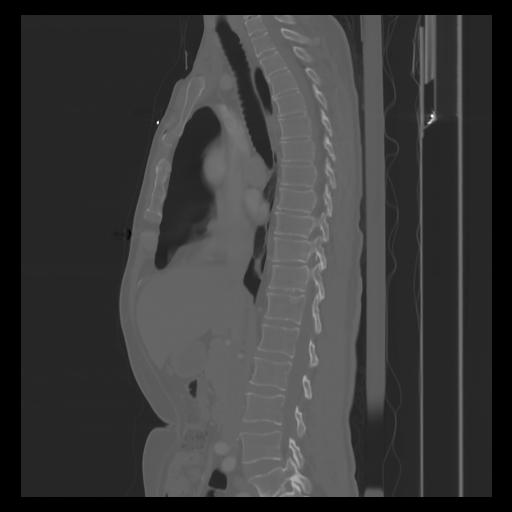

30 CUERPO,CE,Sagittal,3.000,CUERPO,Sagittal,